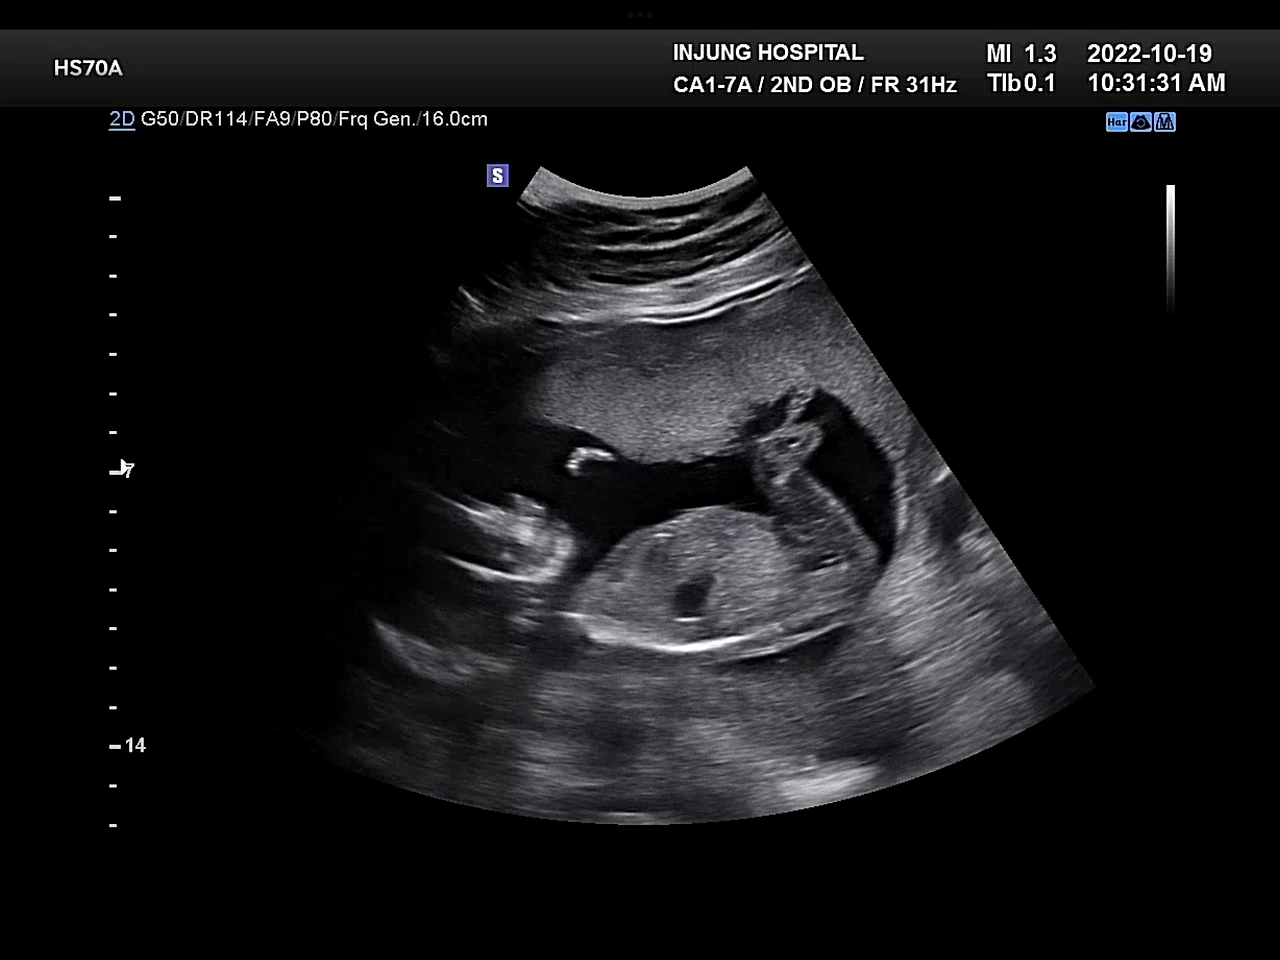

16주 병원진료, 아이 크기는 17주 정도의 크기라고 했다. 아인이는 작게 태어난 편이었는데, 의사 선생님이 그럴 경우 둘째가 너무 크면 분만할 때 힘들 수 있다고 하셨다. 체중도 많이 늘어난 편이니 먹는 걸 조절하라고. 입덧도 거의 끝나서 이제 신나게 먹고 있는 중이었는데….. 의사 선생님이 특히 빵이나 과일을 조심하라셨다. 하필이면 젤 땡기는 음식들….

귀여운 옆모습, 귀여운 발꼬락

포도는 아들이었다. 의사 선생님이 초음파기계를 포도의 엉덩이 쪽에 갖다 대자 아들임을 알리는 그 무언가가 바로 보였다. 의사 선생님도 “따로 말 안 해줘도 아시겠죠?”라며 웃으셨다. 그게 너무 선명하게 보여서 나도 쌤이랑 같이 웃었다. 임신증상이나 입덧증상도 아인이랑 묘하게 달랐는데 그래서 그랬나 싶기도 했다. 암튼 우리 아들 안녕!